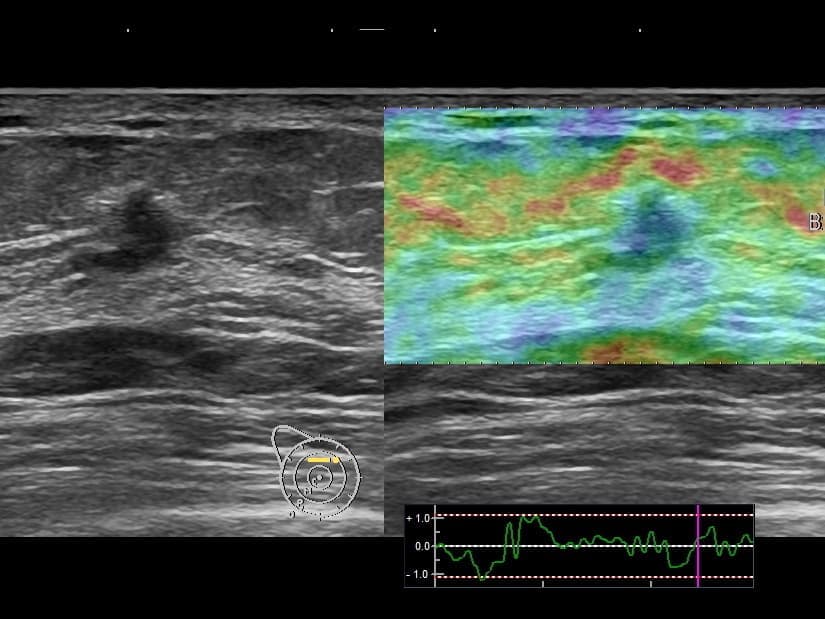

• 乳腺超音波検査:腫瘤の硬さをみるエラストグラフィーの機能もあります。若い女性の乳癌の発見にはマンモグラフィーよりも超音波検査が有用な場合もあります。